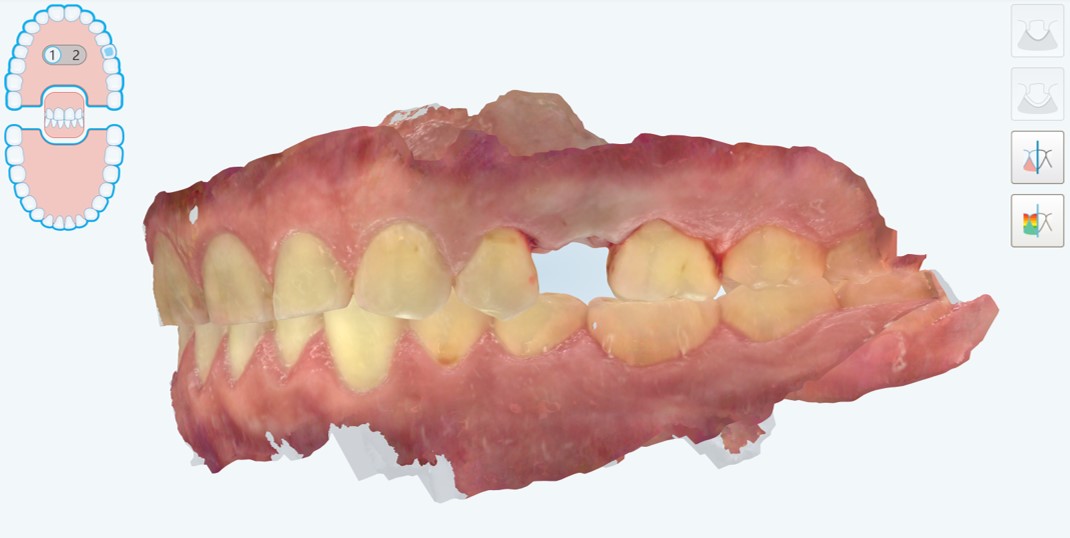

Presentiamo un caso di riabilitazione di edentulia singola attraverso una corona supportata da impianto prodotto con moderna tecnologia di laser sintering. Il paziente, maschio di 45 anni senza particolari problemi di salute generale, con una buona salute orale, fumatore ma non bruxista, si presentava alla nostra attenzione per la risoluzione di un problema di edentulia singola a carico dell’elemento #25 (secondo premolare superiore di sinistra) (Fig. 1,2).

Situazione pre-operatoria, visione laterale

Fig. 1. Situazione pre-operatoria, visione laterale.

Situazione pre-operatoria, visione occlusale

Fig. 2. Situazione pre-operatoria, visione occlusale. Il secondo premolare di sinistra (#25) è stato da poco estratto perché non più recuperabile e il paziente.